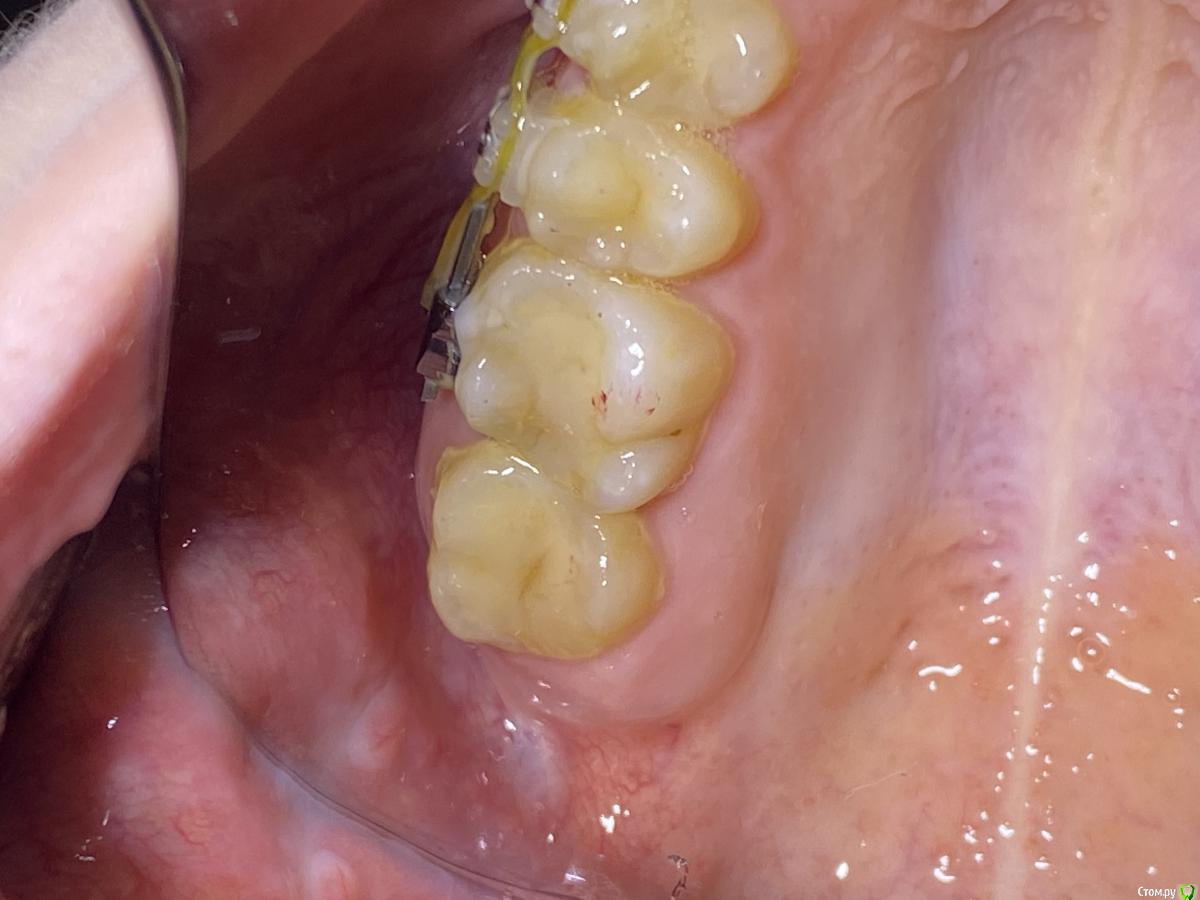

It'sGeorgy Опубликовано 13 декабря, 2019 Автор Поделиться Опубликовано 13 декабря, 2019 Повторно не нашёл открытого ОАС. Рото-носовая и носо-ротовые пробы отрицательны. Через пол года повторное КТ, буду смотреть на состояние пазухи и состояние лунки. Если хуже не станет, то, как написали выше, буду считать пациентку выздоровевшей. В прикреплениях - вероятное место лунки(не сравнивал ещё по КТ). 2 Ссылка на комментарий

Дмитрий М Опубликовано 16 декабря, 2019 Поделиться Опубликовано 16 декабря, 2019 Через пол года повторное КТ, буду смотреть на состояние пазухи и состояние лунки. здесь зондом проверили? визуально похож на выводной проток Ссылка на комментарий

It'sGeorgy Опубликовано 18 декабря, 2019 Автор Поделиться Опубликовано 18 декабря, 2019 2222.jpgздесь зондом проверили? визуально похож на выводной проток Если честно, сейчас сложно сказать уже. Вроде как все что можно и нельзя прозондировал. Но на выводной проток окоушной, да, действительно, похоже. Ссылка на комментарий

Дмитрий М Опубликовано 18 декабря, 2019 Поделиться Опубликовано 18 декабря, 2019 Если честно, сейчас сложно сказать уже. Вроде как все что можно и нельзя прозондировал. Но на выводной проток окоушной, да, действительно, похоже.только для околоушного локализация не типичная Ссылка на комментарий

It'sGeorgy Опубликовано 18 декабря, 2019 Автор Поделиться Опубликовано 18 декабря, 2019 только для околоушного локализация не типичная Да, по хорошему, медиальнее на 5-6 мм быть должен. Не исключено, что большим интраоральным зеркалом просто отодвинули преддверие + брекеты были, на пару мм могли семерку сдвинуть. Ссылка на комментарий